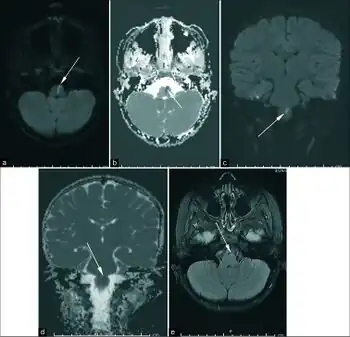

Weber's syndrome is the only form of alternating hemiplegia that is somewhat easy to diagnose beyond the general criteria. Although Weber's syndrome is rare, a child born with the disorder typically has a port-wine stain on the face around the eye. While the port-wine stain does not necessarily mean the child has Weber's syndrome, if the port-wine stain involves the ophthalmic division of the trigeminal nerve than the likelihood of it being weber's syndrome greatly increases. If a port-wine stain around the eye is found, the patient should be screened for intracranial leptomeningeal angiomatosis. Magnetic resonance imaging (MRI) can be used to determine the presence and severity while computed cranial tomography can be used to determine the effect. MRI is the preferred diagnostic test on children presenting with port-wine stain. Other imaging techniques can be used in addition to further determine the severity of the disorder. The initial diagnosis is made based on the presence of neurologic and ophthalmic disease but the disease progresses differently in each patient so after initial diagnosis the patient should be monitored frequently in order to handle further complications resulting from the syndrome.[7]